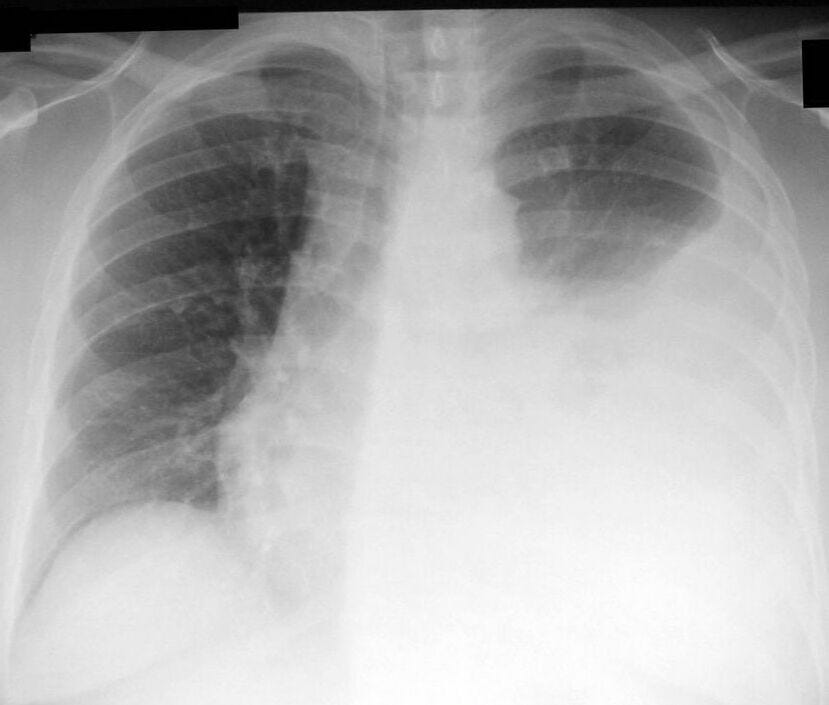

Should pleurodesis or PleurX drain be 1st-line Rx for malignant pleural effusion?

There are an estimated 200,000 pleural effusions due to malignancy each year in the U.S. alone, and these represent an important cause of suffering and limitation in functional ability for people living with advanced cancer. Pleurodesis (using talc or other sclerosants) and placement of indwelling pleural catheters are both accepted, reasonable approaches to the management of malignant pleural effusions. In a recent JAMA article testing the two treatments for malignant pleural effusion, both appeared to be equally efficacious at relieving dyspnea.